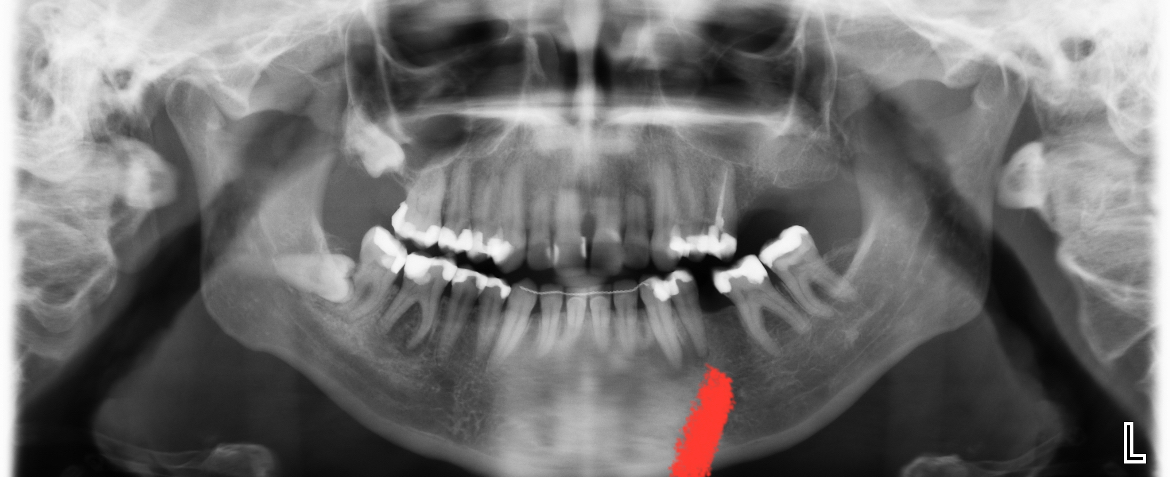

Wie kan mij helpen. Na lang uitstellen heb ik toch maar een afspraak gemaakt bij de kaakchirurg ingepland om mijn verstandskies eruit te halen die dwars ligt. (23 februari) De kiest daarnaast blijft staan en in de andere kies die daar naast staat zou een ontsteking zitten in de wortelpunt. Ik schrok heel erg van de kosten dus twijfel nu wat te doen. Of een wortelkanaalbehandeling of door de vele vullingen die al in deze tand zitten deze ook maar te trekken. Ik ben erg onzeker over mijn gebit door alle vullingen die ik heb in met name de kiezen. Aan de andere kant van mijn gebit is namelijk ook al een kies getrokken omdat deze gewoon heel zwak was en constant afbrak.

Ik hoop dat ik nog wel even met mijn tanden kan doen. Wat vind je op dit moment van de foto?

Zie je een grote ontsteking? Of kan dit nog behandeld worden met een antibiotica kuur.

Verstand kies verwijderen, wkb 46 ( eerste grote kies flinke ontsteking niet met AB kuur goed te krijgen) later kroon ( als u kiest voor behoud met vaste voorzieningen).....